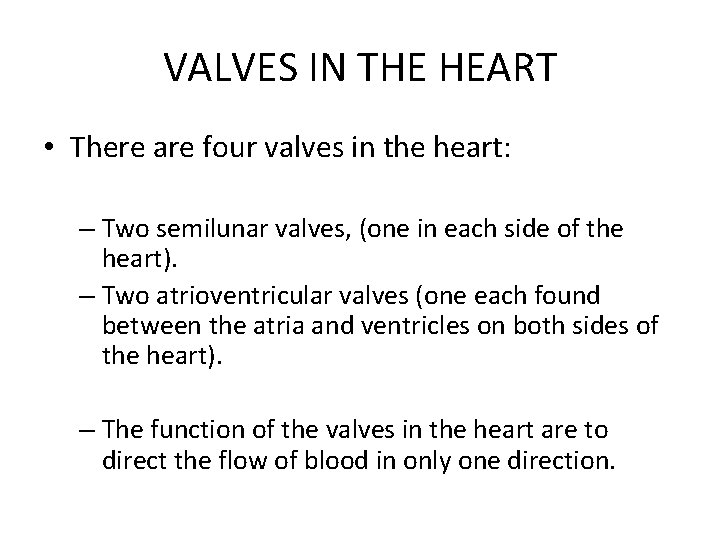

VALVES IN THE HEART • There are four valves in the heart: – Two semilunar valves, (one in each side of the heart). – Two atrioventricular valves (one each found between the atria and ventricles on both sides of the heart). – The function of the valves in the heart are to direct the flow of blood in only one direction.